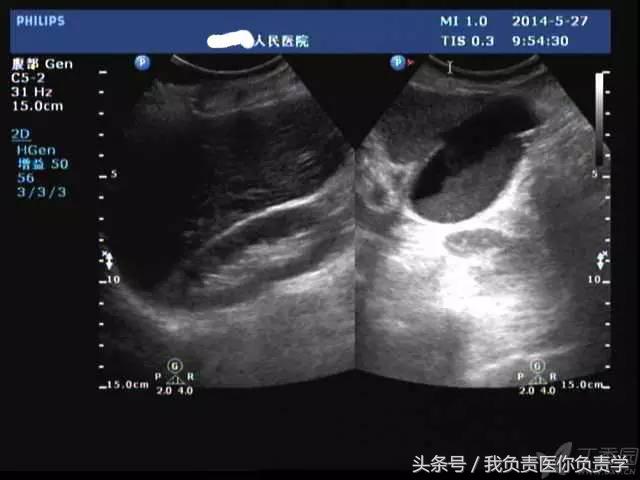

典型病例 4

(由丁香园注册用户「哥特复兴5」提供)

患者女,79岁,晚餐后出现脐周疼痛数小时急诊。患者无发热,实验室检查示白细胞14×109/L,临床考虑阑尾炎,行超声检查所见如下:

图1示胆囊充盈差,囊壁明显增厚,胆囊周围可见无回声环绕分布

图2为高频探头所见,示胆囊壁肝床侧回声中断,周围可见无回声分布

超声诊断为胆囊穿孔,后经手术证实。